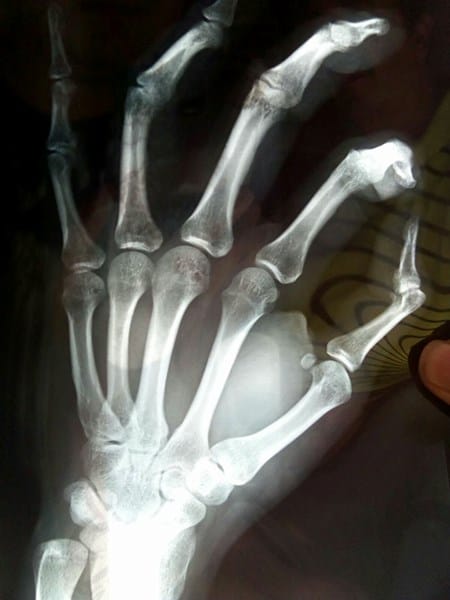

Hace aproximadamente un mes y medio, tuve un accidente en el cual todo mi peso corporal cayó sobre mi dedo pulgar, provocando un enorme dolor, una hinchazón bastante grande y falta de movimiento. Debido a mi carga académica, no pude revisarme el dedo con un especialista sino hasta 3 semanas después, el cual me lo inmovilizó por dos semanas ya que él encontró que se trataba de la inflación entre la falange proximal y el metacarpo, ya pasaron las dos semanas y al retirar la férula noté que mi dedo no puede ser flexionado para el interior de la mano, no sé qué debería hacer al respecto, me gustaría saber la opinión de un experto para poder conocer si el diagnóstico fue erróneo y debería ir de nuevo con un especialista. Anexo la foto de la radiografía. Muchas gracias de antemano.